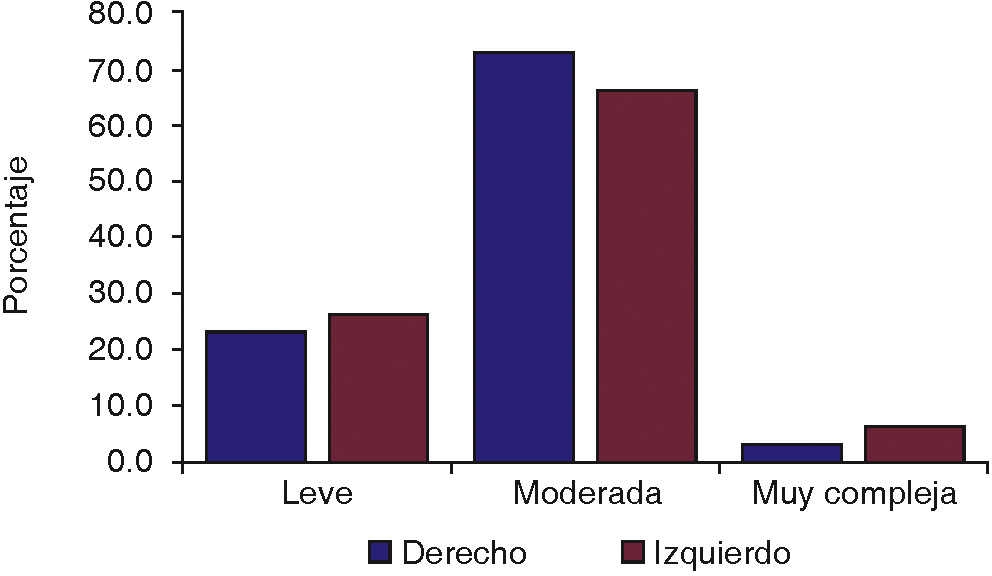

De los 30 pacientes incluidos en el estudio, 15 fueron del sexo femenino y 15 del sexo masculino. Fueron agrupados por edad, 8 pacientes de 16 a 19 años, 15 pacientes de 20 a 23 años, y 7 pacientes de 24 a 27 años (Figura 4). Se catalogaron por dificultad de extracción según la clasificación de Pederson17 en leve, moderada y muy compleja, con resultados de 7 leves, 22 moderadas y una muy compleja en el lado derecho y 8 leves, 20 moderadas y 2 muy complejas en el lado izquierdo (Figura 5).

Por último, la dificultad de la extracción dentaria fue calculada mediante la escala de Pederson.17 Los mejores valores medios se presentaron en el grupo experimental y en el subgrupo denominado como extracción de leve complejidad; aunque estadísticamente no indica influencia la complejidad de la cirugía con la cicatrización ósea.